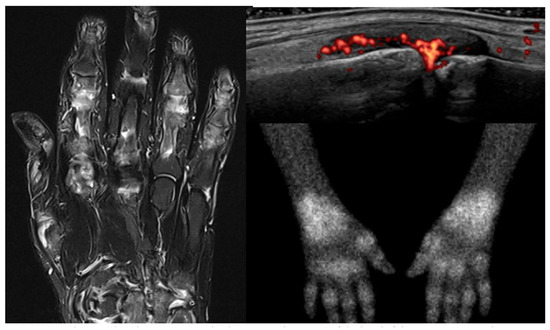

Despite important advancements in arthritis research, significant challenges remain, particularly in the early diagnosis of these conditions and the development of personalized treatments tailored to individual patients. This Special Issue aims to address these issues by focusing on innovative diagnostic methods, such as advanced imaging techniques, and a deeper understanding of disease mechanisms. It will also explore cutting-edge treatments, including disease-modifying anti-rheumatic drugs (DMARDs), biologics, and targeted therapies.

A key goal of this Special Issue is to improve how healthcare professionals differentiate between similar types of arthritis, enabling quicker and more accurate diagnoses, and to better assess the extra-articular manifestations of these diseases.